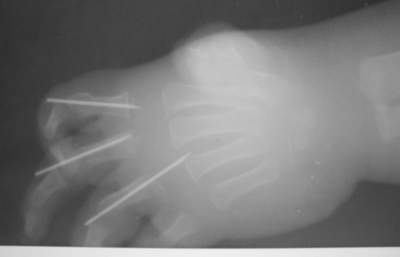

Dear collegues,В прошлое воскресенье (по дежурству) привезли одного ребеночка из соседнего городка.Травма - ребенок засунул руку в электромясорубку за 2 суток до попадания к нам (в пятницу).По месту жительства - ПХО, спицы....

До сих по не могу смотреть без содрогания.Мальчику - 2 годика, правая ручка.Кистевики говорили, что 2,3 и 4 пальцы придется отрезать, попробуют разве что только побороться за основные фаланги (завтра узнаю подробнее ибо уже прошла неделя).P.S. Судя по поведению матери в приемном покое мясо крутила именно она... а отец был так НЕХОРОШО и ЗАДУМЧИВО УГРЮМ...-- Best regards,~~~~~~~~~~~~~~~~~~~~~~~~~~~~~~~~~~~~~~~~~~~~~~Aleksey V. Mozgounov

Вроде бы на представленных фото пальцы жизнеспособны... ( снимки сразу после обработки или на момент госпитализации к вам, 2 дня спустя ?)

На 3-4 сутки обычно становится очевидно - что выживет, а что уйдет при повторно обработке.

Если перфузия пальцев сохранится, то прогноз должен быть благоприятным - у детей удивительные репаративные способности. При первичной обработке таких повреждений интаоперационно невозможно определить демаркацию травмы мягких тканей, поэтому обработка по сути сводится к тщательному промыванию ран и адаптации кожных лоскутов редкими швами, после 3-4 дней, когда зона демаркации становится различимой - повторная обработка.

Я бы не стал ушивать такую кисть как на * швейной машинке* - эстетично выглядит сразу после обработки, но практически не дренируемая рана.